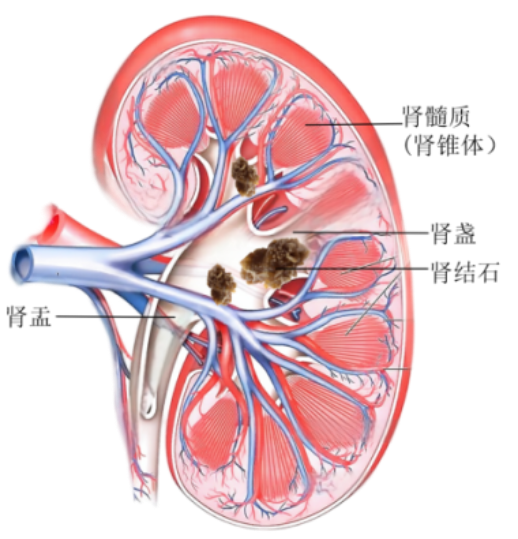

图1 普通肾脏伴肾结石的剖面示意图(结石位于肾盂及肾盏)

图2 髓质海绵肾合并肾结石剖面示意图(结石位于肾髓质的集合管内)

2.结晶成核。滞留的尿液让钙、磷、草酸等分小子浓度飙升,并逐渐达到过饱和状态,再加上其他相关促石因子的干预,矿物质们开始凝聚成微结晶,从而形成以草酸钙或磷酸钙为核心的结石。他们像葡萄串般填充在扩张的集合管里,CT扫描时会出现标志性的“花簇状”影像。